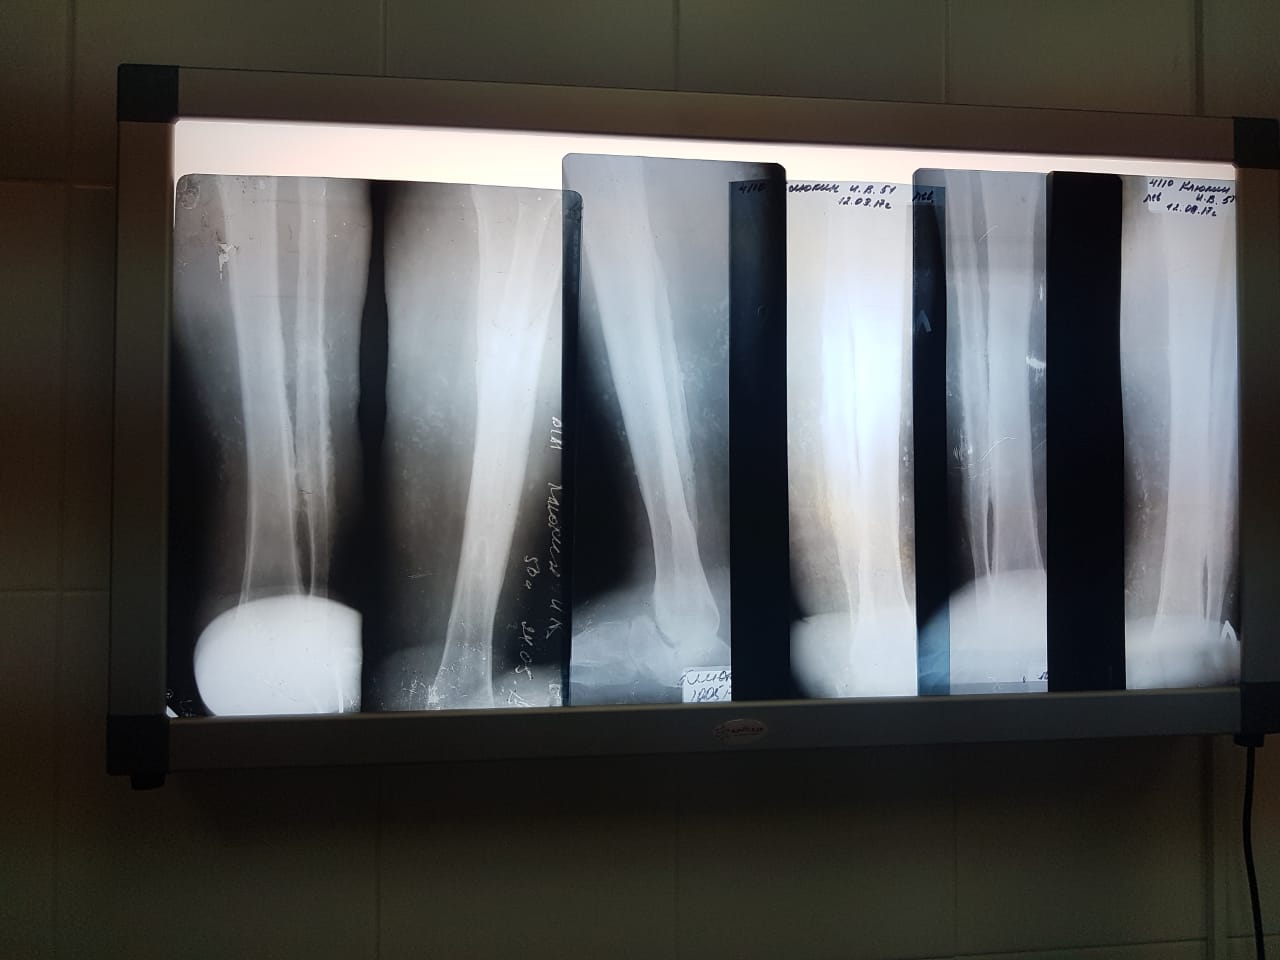

[Ortho] Остеомиелит. Какие будут мнения, коллеги?

п╞ я│п╨п╩п╬п╫я▐я▌я│я▄ п╨ п╟п╪п©я┐я┌п╟я├п╦п╦. п п╒ п╫п╟п╥п╫п╟я┤п╣п╫п╬.